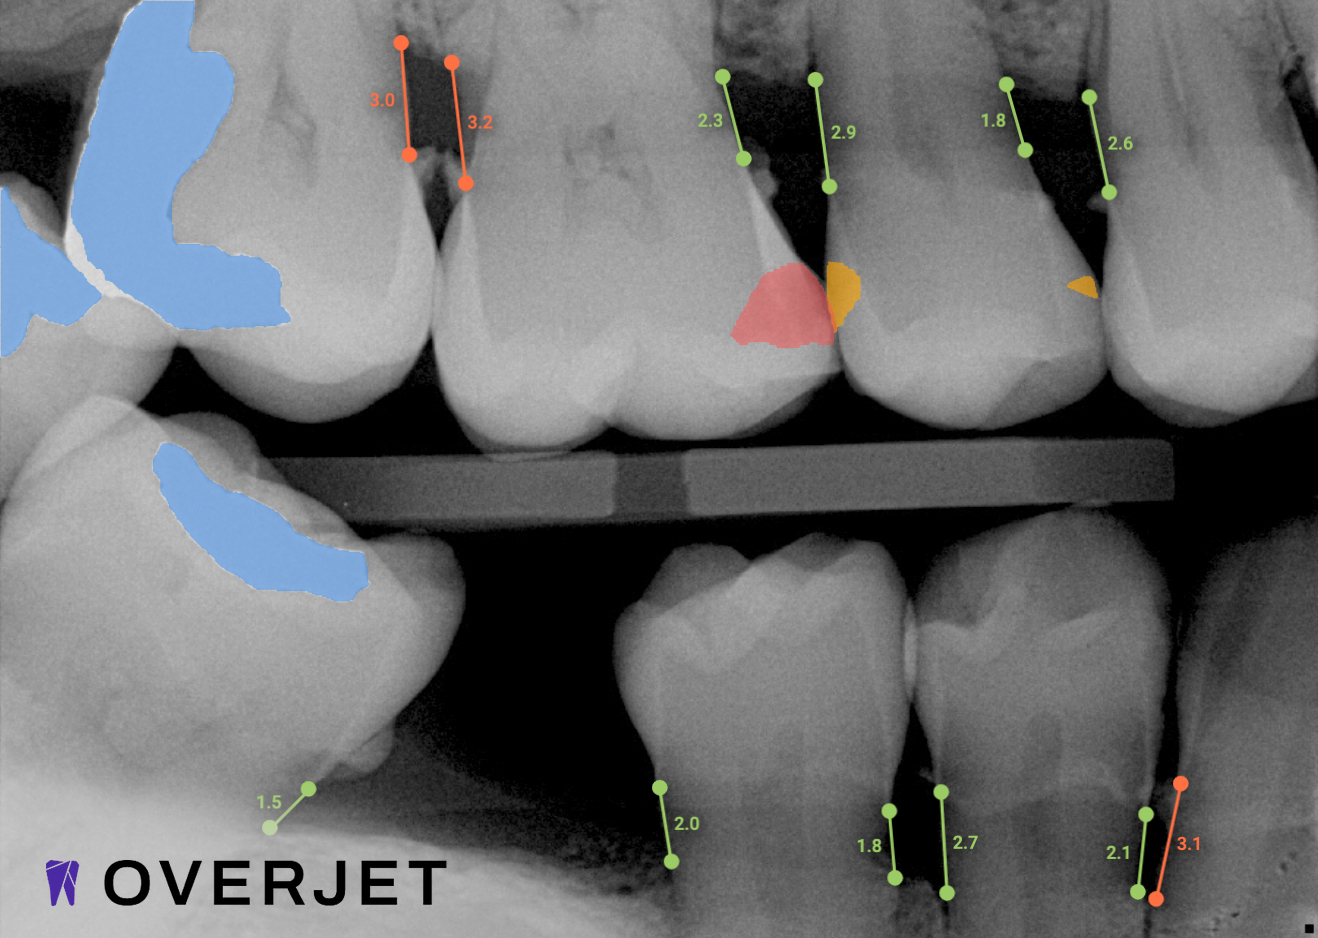

Overjet’s artificial intelligence technology transforms traditional black-and-white X-rays by adding a layer of data that instantly outlines decay (cavities) and measures bone loss. This makes it easy for you to see your results alongside your dentist.  It’s like getting a second opinion delivered instantly. With Overjet’s analysis and easy-to-read presentation, you will have the information you need to make an informed decision about your oral health. Together, we’ll review your findings and discuss the best steps to take to achieve your goals.

Overjet’s artificial intelligence technology transforms traditional black-and-white X-rays by adding a layer of data that instantly outlines decay (cavities) and measures bone loss. This makes it easy for you to see your results alongside your dentist.